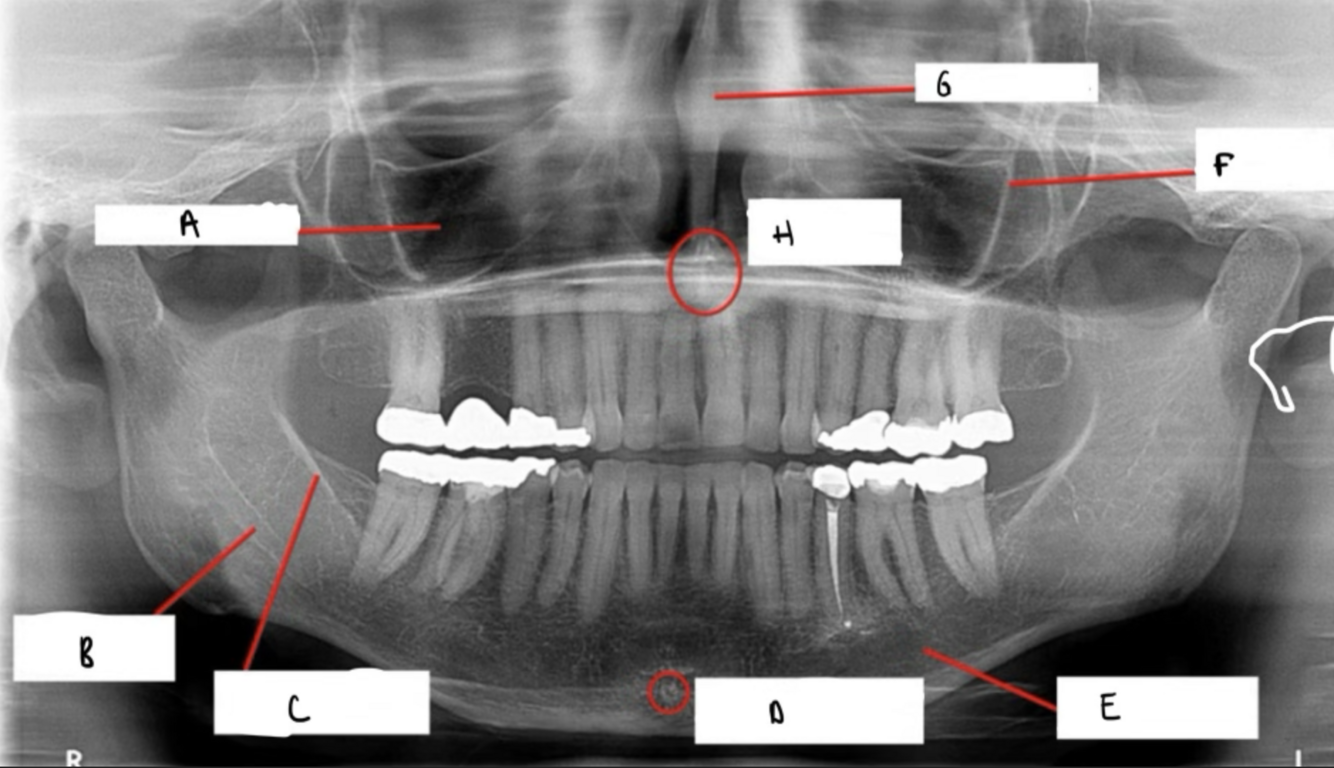

Label the following image:

A

1. red: nasal cavity

2. green: conchae

3. yellow: nasal septum

How well did you know this?

A: maxillary sinus

B: mandibular canal

C: internal oblique ridge

D: genial tubercle & lingual foramen

E: submandibular fossa

F: zygomatic process

G: nasal septum

H: anterior nasal spine